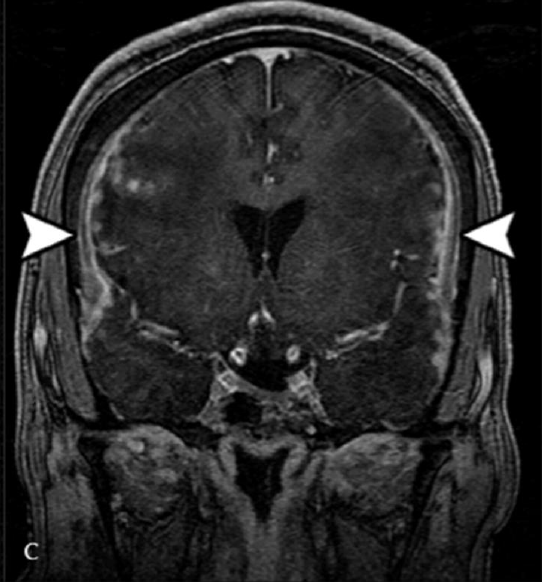

白质低信号(DWM)如何助力医生区分 NKH、MOG 脑炎与硬膜下血肿?